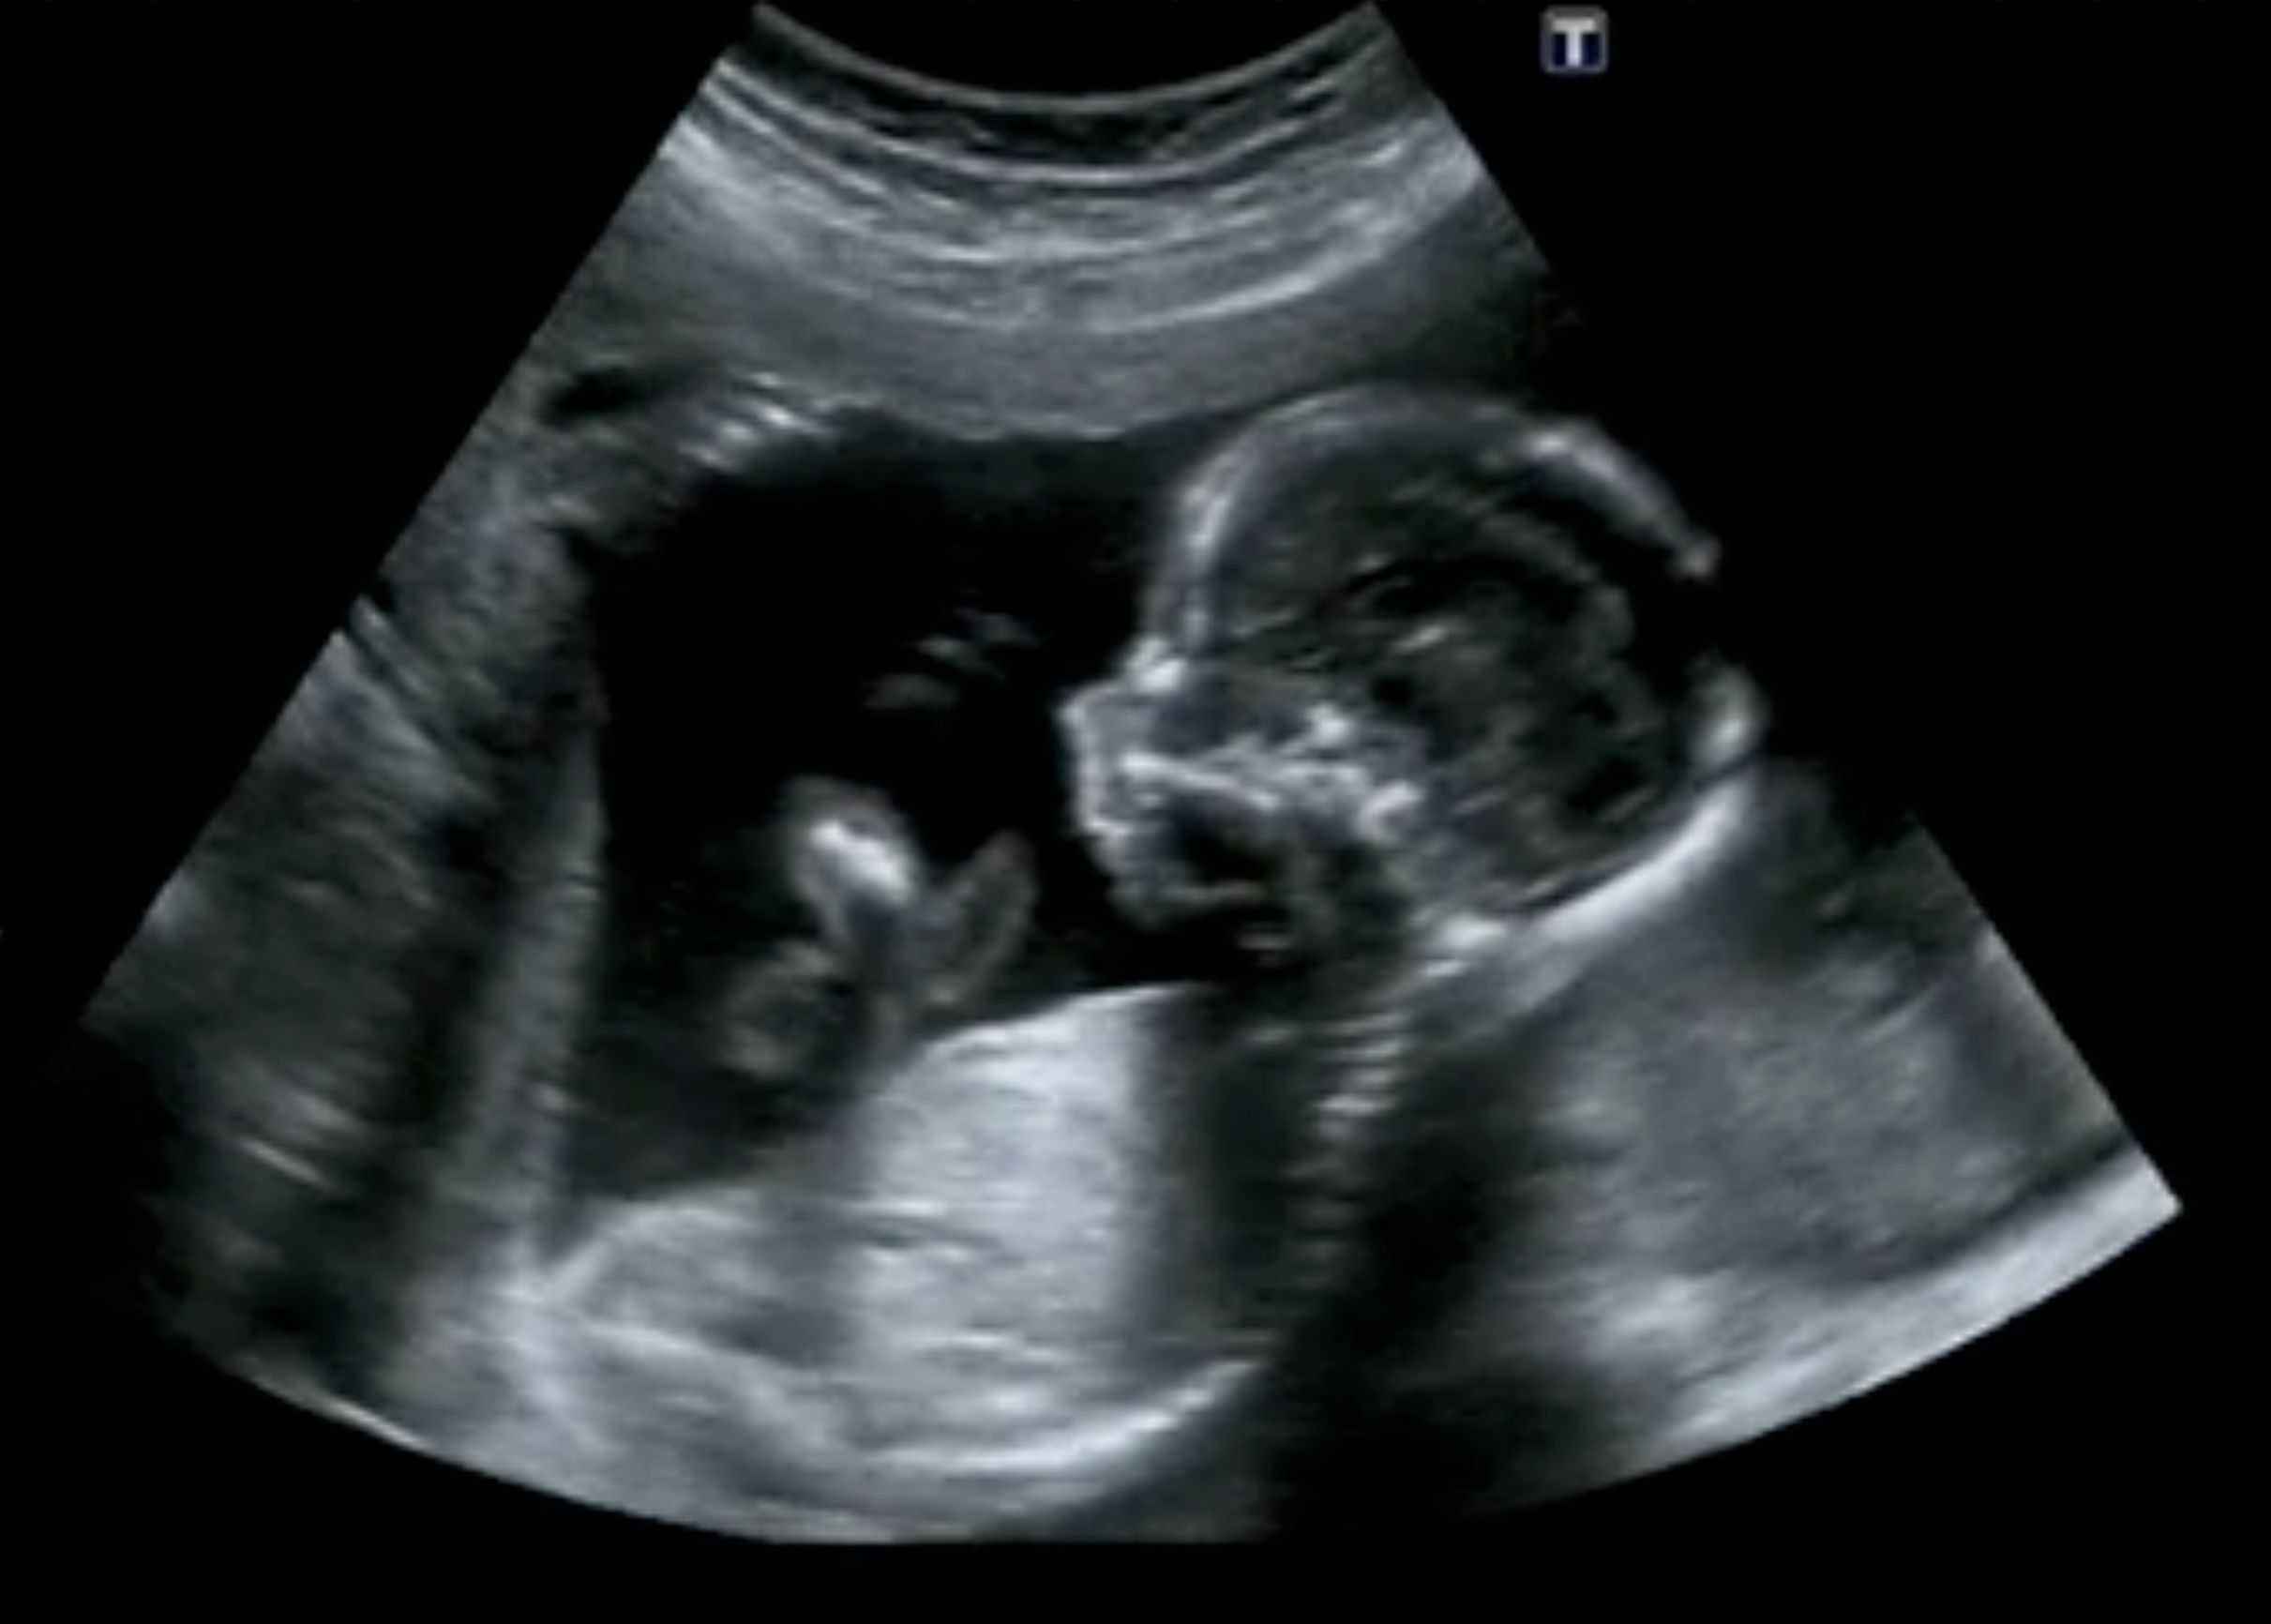

Pada fase ini, kelopak mata janin telah sepenuhnya terbentuk namun masih belum bisa terbuka hingga memasuki trimester ke-2. Selain itu, organ seksual dalam tubuh janin juga mulai terbentuk walaupun masih belum bisa terlihat melalui pencitraan ultrasonografi (USG).

Janin juga mulai bisa membuka lengan dan menggerakkan jari-jarinya karena sistem saraf di otaknya telah terbentuk sepenuhnya. Wajah janin juga sudah mulai terbentuk sempurna dengan posisi mata dan telinga yang telah berada pada tempatnya.